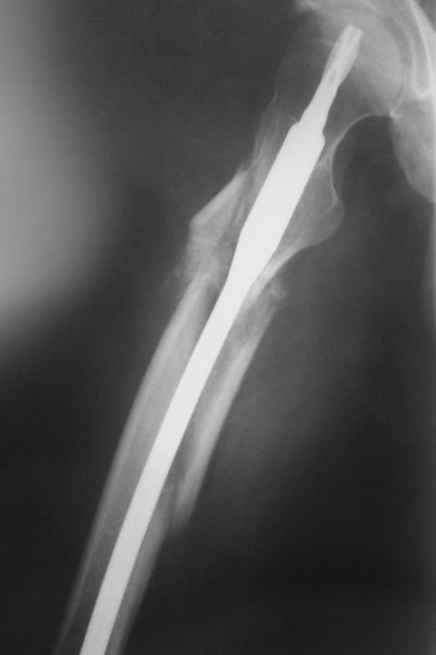

Отломок, расположенный так, как на показанных рентгенограммах бедра, обычно на снимках в 1-2 мес. уже располагается ближе к диафизу и

включается в мозоль.

На операции я оставил осколок в области приводящих мышц бедра (ни пальпаторно, ни спицей сдвинуть не смог, "заклинило" насмерть). Фото спустя 2 месяца после операции (PFN).

Только сейчас пациент стал более или менее активным. Сразу после операции жалобы на сильные боли при отведении и приведении бедра в области отломка. Сейчас отломок пальпируется и пациент испытывает дискомфорт, хотя амплитуда движений объективно прогрессирует.